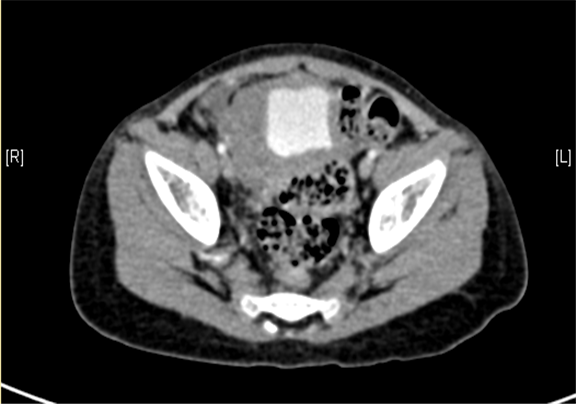

下腹部增强CT示右下腹腔内巨大软组织块影并右肾、输尿管积水。

术前CT检查:

静脉期